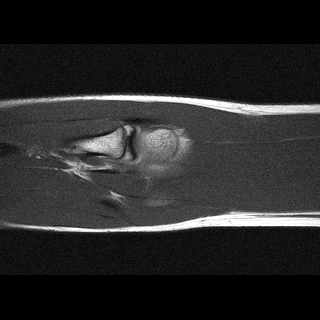

Orientation-specific examples grouped by anatomy. Select a category to view axial, coronal, and sagittal samples.

Sagittal

Sagittal sample